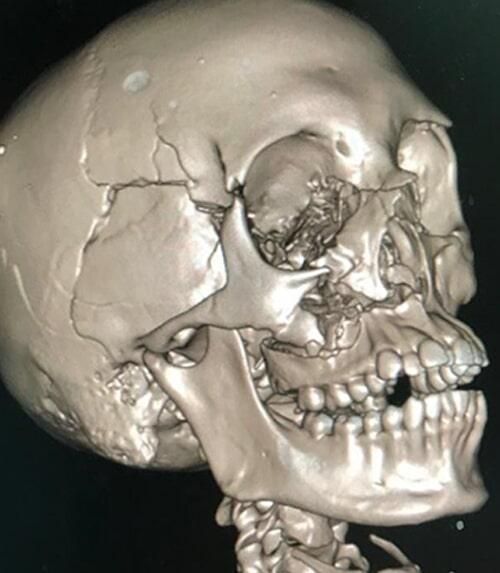

FRACTURA DE ORBITA,

MAXILAR Y MANDÍBULA

Si tienes alguna fractura maxilar y/o mandibular, o te dijeron que te fracturaste, danos la oportunidad de valorarte y brindarte opciones de tratamiento para un pronta recuperación